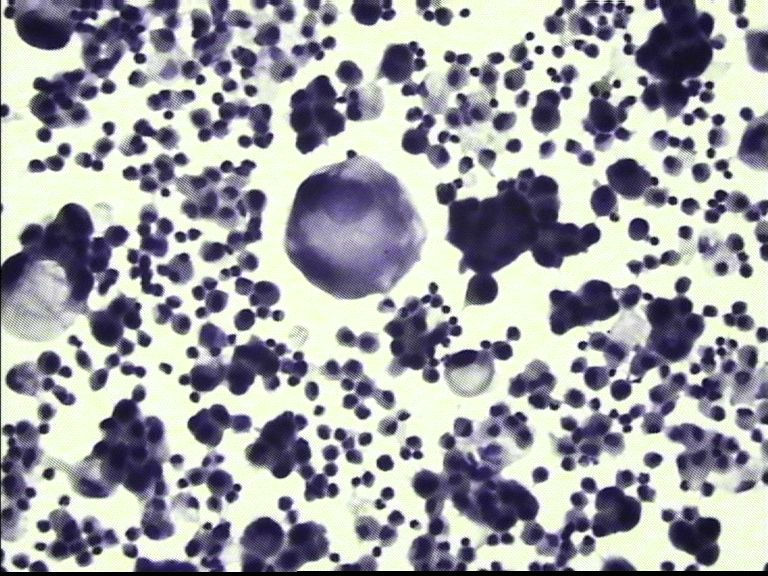

胸水 男67岁

• 胸水 男67岁图3

图3